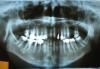

ivanna Опубликовано 17 августа, 2010 Автор Поделиться Опубликовано 17 августа, 2010 (изменено) Не прочитала, поспешила. Вот снимок, только с еще неудаленным вторым зубом. Изменено 17 августа, 2010 пользователем ivanna Ссылка на комментарий